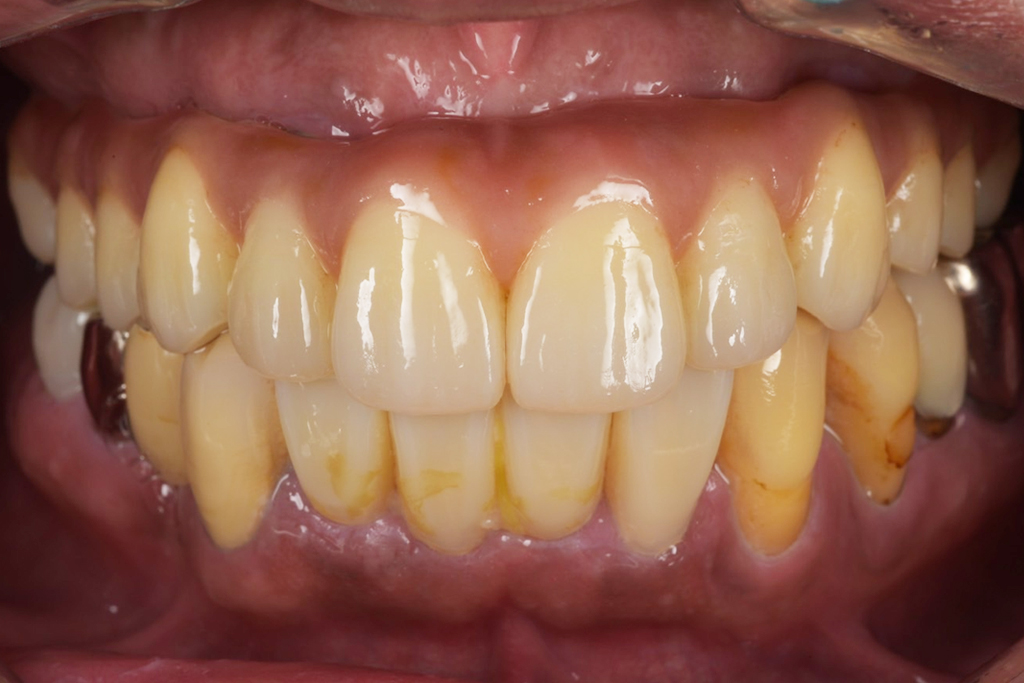

今回は噛めることと見た目の改善を目的として上顎はダメな部分は抜歯をし、インプラントを入れました。

現在では硬いものもかめてやってよかったと言われて私は満足しかありません。

かなりボロボロでもこのような難症例であろうと私は治療ができると自信がつきました。

今では定期検診でしっかりと予防を行っていただいています。